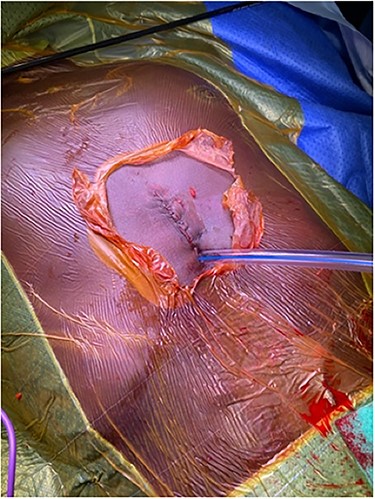

The operation was conducted with the patient lying in a supine position. A single incision was made distally to the xiphisternum, the dissection was then carried out along the linea alba to reach the anterior mediastinum posteriorly to the sternum. The sternum was then lifted using a Rultract® Skyhook Retractor to improve both the exposure of the pleural cavities and the working space (Fig. 3). To further increase the working space double tube ventilation was used. When operating on the right chest cavity, we excluded the ventilation of the right lung and vice versa for when working on the left lung. A 30° 10 mm diameter scope was used to visualize the pleural cavities.

Image showing the sternum being lifted using a Rultract® Skyhook Retractor to allow good access to the pleural cavities.